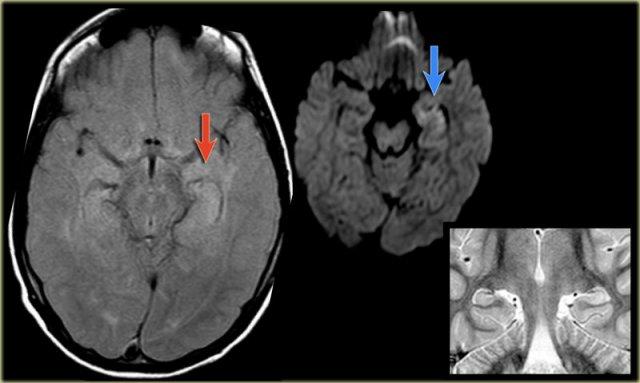

Hình ảnh cho thấy xơ cứng thùy thái dương trong với hải mã tăng tín hiệu và teo nhỏ (mũi tên đỏ), kèm theo giãn thứ phát sừng thái dương trái của não thất bên trái.

Cũng cần lưu ý tình trạng tăng tín hiệu dưới vỏ não kết hợp ở thùy thái dương trái, gợi ý loạn sản vỏ não khu trú.

Xơ cứng thùy thái dương trong bên trái. Gliosis kín đáo của hải mã trái (mũi tên xanh dương) và teo não (mũi tên vàng).

Bệnh nhân 35 tuổi với động kinh thùy thái dương kháng trị.

MRI cho thấy tăng tín hiệu kín đáo của hải mã trái trên chuỗi xung FLAIR axial (mũi tên xanh dương) và teo hải mã trái trên hình ảnh coronal (mũi tên vàng).

Bệnh nhân được điều trị thành công bằng phẫu thuật cắt hạnh nhân – hải mã bên trái.